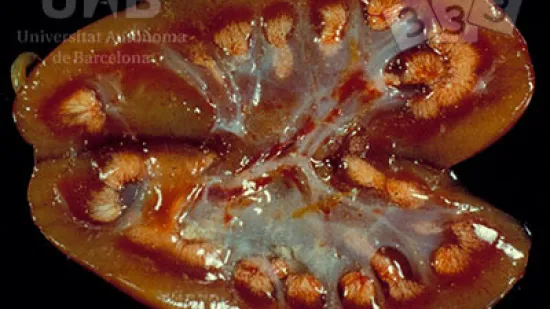

Semaine du 26-Avr-2021

Quelle lésion peut être observée sur ce rein ?